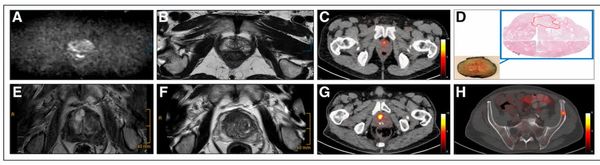

Study: PSMA PET/CT Changed Treatment Plans for Over a Third of Men with Prostate Cancer

In a new review from the European Society of Urogenital Radiology (ESUR), researchers discuss the merits and limitations of PSMA PET/CT and whole-body MRI (WB-MRI) for patients with advanced prostate cancer.